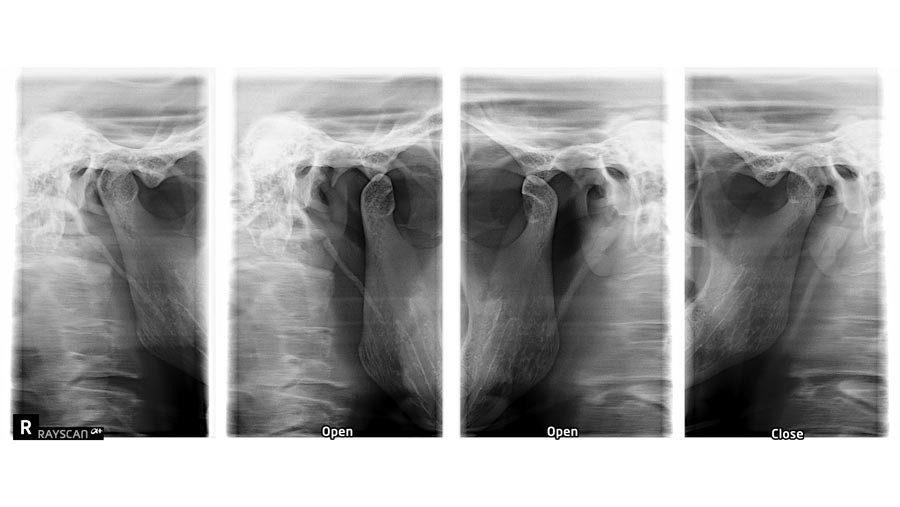

Jeśli masz problemy z bólem szczęki, trudności w otwieraniu ust, trzaskami czy napięciem w okolicach stawów skroniowo-żuchwowych, lekarz kierujący może zlecić wykonanie RTG SSŻ – w Poznaniu zrobisz je w naszych placówkach. Badanie to pozwala na ocenę zmian w stawie zarówno w pozycji zamkniętej jak i rozwartych ust, co jest istotne dla diagnozy schorzeń takich jak dysfunkcja stawu skroniowo-żuchwowego (TMD), zwyrodnienia czy urazy.

Badanie rentgenowskie stawów skroniowo-żuchwowych (SSŻ) pomaga ocenić strukturę oraz funkcję, zarówno w pozycji zwartej, jak i przy maksymalnym rozwarciu ust. Pozwala to na dokładne przeanalizowanie kondycji stawów oraz ich wpływu na funkcjonowanie zgryzu. RTG SSŻ odgrywa istotną rolę w diagnostyce i planowaniu leczenia w wielu dziedzinach stomatologii, w tym w chirurgii stomatologicznej, ortodoncji oraz terapii zaburzeń okluzji. Wykrywa nieprawidłowości, takie jak zmiany zwyrodnieniowe, przemieszczenia krążków stawowych czy dysfunkcje stawów.

Badanie rentgenowskie stawów skroniowo-żuchwowych, zarówno w pozycji zwartej, jak i rozwartych, jest szybkim, bezbolesnym i mało inwazyjnym badaniem. Podczas badania pacjent przyjmuje pozycję stojącą, która zapewnia właściwe ustawienie ciała w celu umożliwienia skutecznego przejścia promieni rentgenowskich przez obszar stawów skroniowo-żuchwowych. W tej pozycji promienie rentgenowskie przechodzą przez struktury stawów, co pozwala uzyskać dokładny obraz ich stanu. Cały proces jest bardzo krótki i trwa zaledwie kilka sekund.